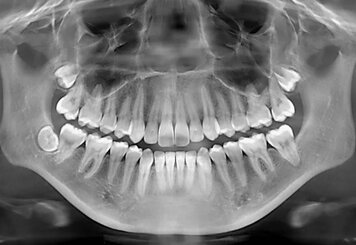

Удаление зубов – это хирургическая процедура, направленная на извлечение одного или нескольких зубов из челюстной кости. Несмотря на то, что звучит это пугающе, в большинстве случаев удаление зубов – необходимая и вполне безопасная процедура, позволяющая